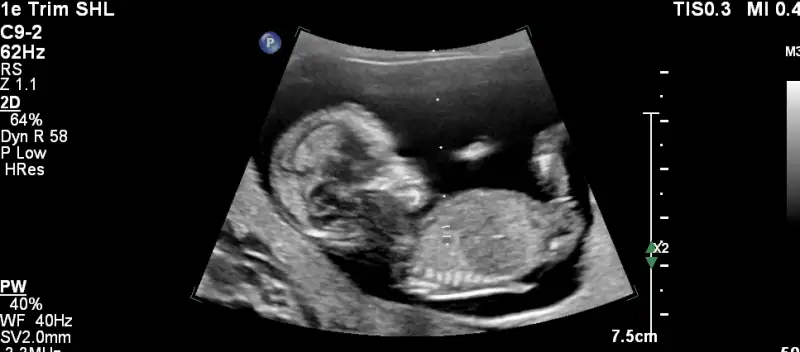

nub teorisi var canim resim at bakalim nasil

• 2.webp

2.webp

14,5 KB · Görüntüleme: 96